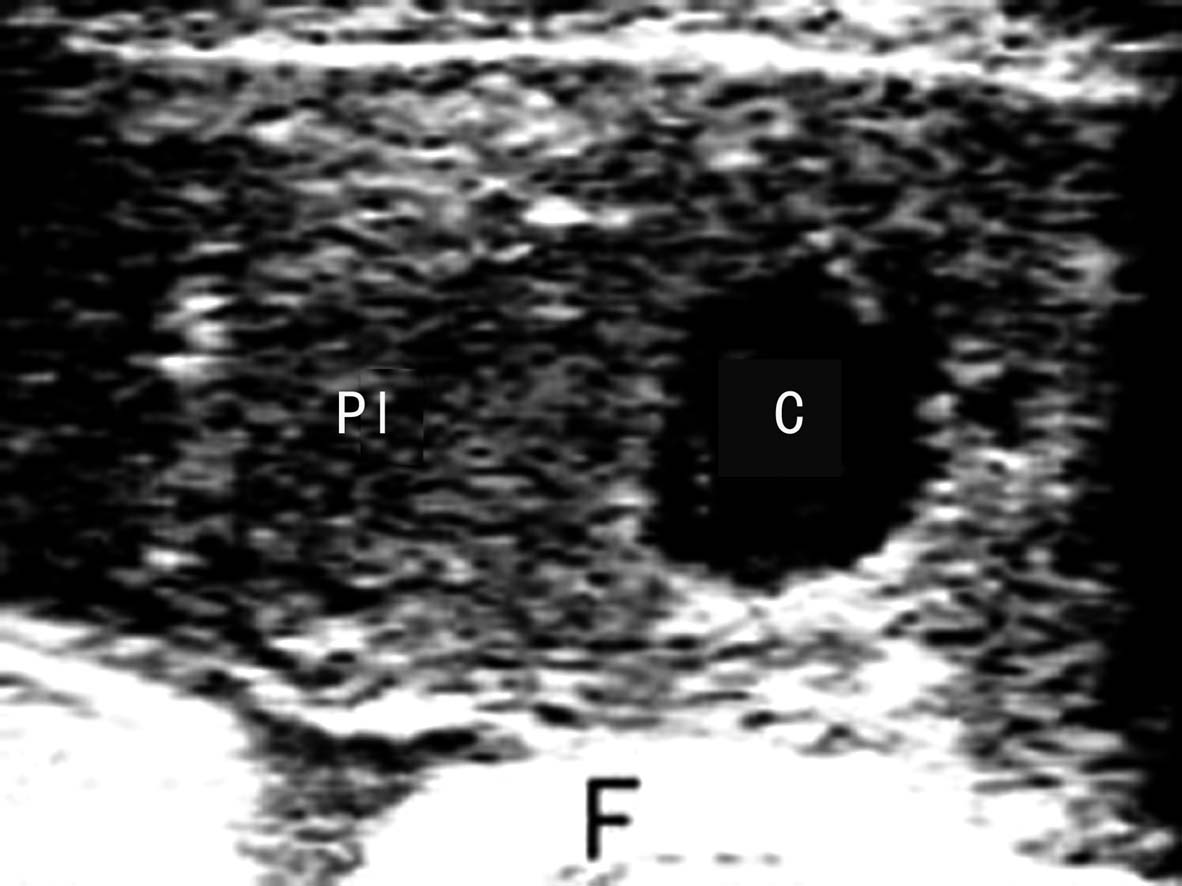

2D-US时胎盘血管瘤显示为胎盘实质内或边缘部位的异常团块回声,形态规则或不规则,边缘清晰,与胎盘实质分界清楚;内部回声差异较大,可以显示为低回声或中等强度的回声,分布不均匀,部分瘤体内部可显示不规则的分隔回声。瘤体多向羊膜腔内突出,如果合并羊水过多,则瘤体在羊水的衬托下多数显示的非常清楚。CDFI检查瘤体内部多无血流显示,有时可以有少量点状血流显示(图1)。

图1胎盘血管瘤